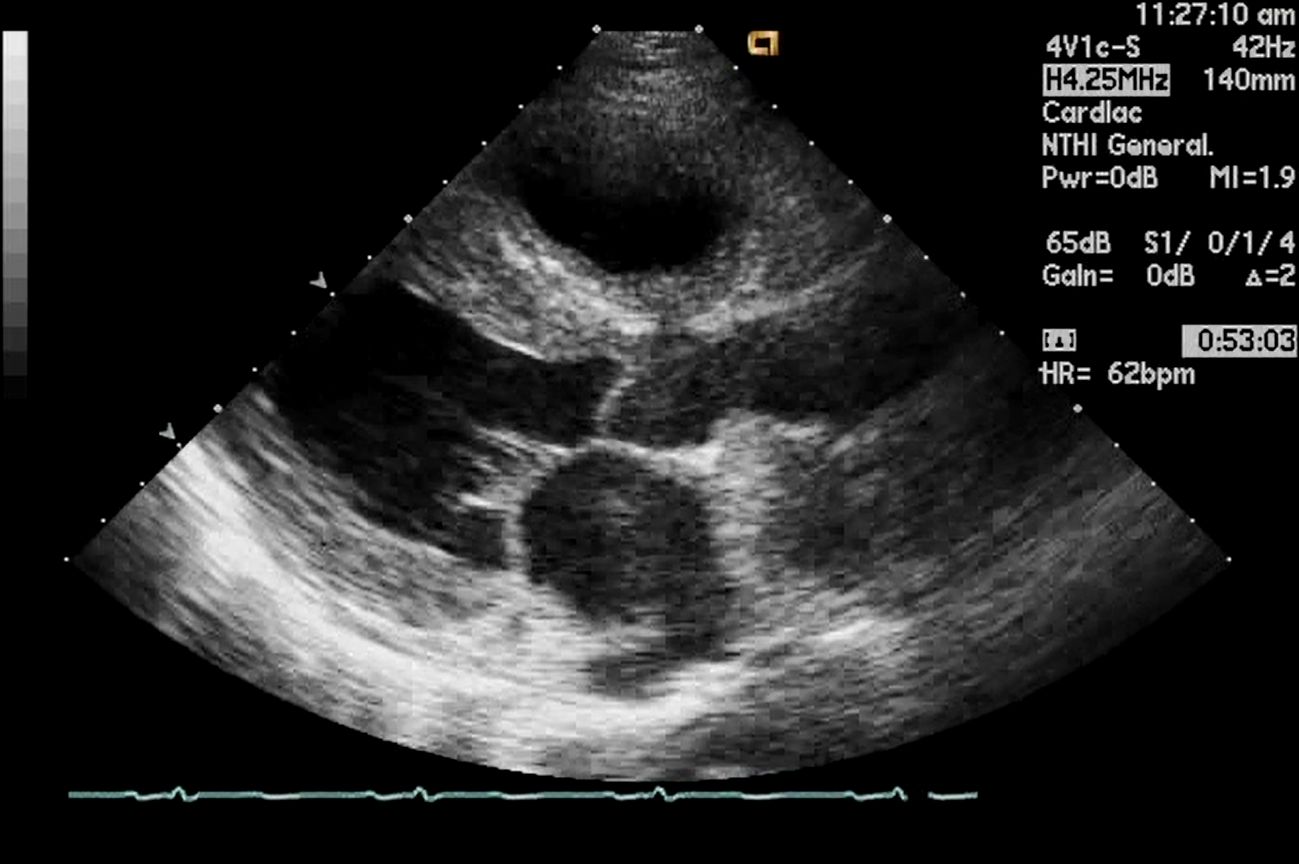

心アミロイドーシス